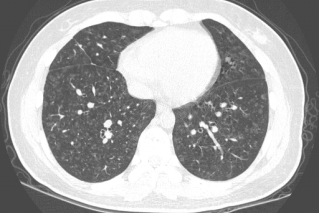

1、所谓急性HP,就是患者接触了较高水平的暴露,例如有患者喜欢饲养鸟类,尤其喜欢宠物鸽子,于是到交易市场去看,在这个过程中,可能出现了间断高水平暴露,于是一些易感个体就在很短的时间内(4到12小时)出现了流感样症状和呼吸道症状,而肺内则出现了一些磨玻璃影。

2、也有一些患者急性发作伴发热,劳力性呼吸困难、乏力和咳嗽,影像表现为小叶中央性的弥漫性的腺泡结节,称之为亚急性HP

3、还有些患者持续性低水平暴露,起病很隐匿,当我们发现时,已经出现了劳力性呼吸困难,干咳,体重减轻和乏力,而影像出现了既有磨玻璃影,也有肺纤维化的表现,称之为慢性HP

图:(从左至右)急性、亚急性、慢性